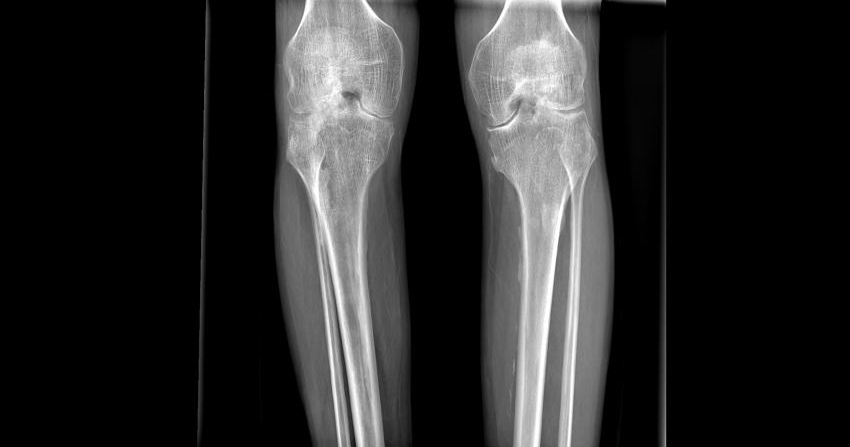

患者术前双膝情况

由于血友病的特殊性,手术方式的选择、围手术期的处理、并发症的预防及处理等问题是一个巨大的挑战。手术中如何精准的截骨、如何安全有效地清除骨赘,又要保证手术中较少的出血,这一个个难题都抛向了医疗团队。